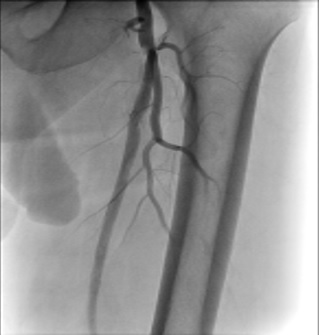

A 70-year-old gentleman with an extensive history of tobacco abuse and a non-ischemic cardiomyopathy presents with left leg claudication for the last 8 years.  His resting ABIs are right 1.00, left .80.  A 6F Ansel (Cook Medical) was selectively engaged into the common femoral artery and in spite of the fact that it was difficult to delineate the origin of the SFA, we passed the .014 Command wire (Abbott Vascular, Abbott Park, Illinois) with the CrossLock™ balloon catheter.  The FrontRunner™ was passed through the Rx port of the CrossLock™ and with the wire pulled back and the CrossLock™ balloon inflated, we were able to pass the FrontRunner™ across the total occlusion.  This was followed by balloon angioplasty and then multiple drug eluting balloons (Lutonix, Bard Peripheral, Tempe, Arizona).  Following this, there was excellent patency and runoff.

Figure 11. The CrossLock™ has been passed over a .014 wire and the FrontRunner™ is also in place. Note the balloon on the CrossLock™ is inflated centering the lumen for passage of the FrontRunner™. It subtends the CTO in real time.